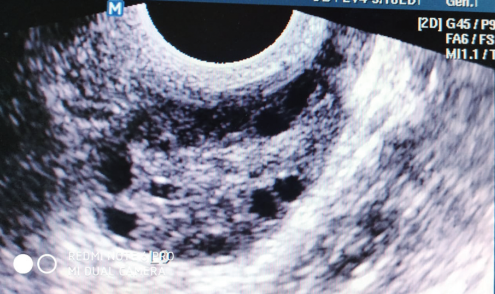

Ultrasonografik Özellikler

Polikistik over görünümü, ultrasonografide overde 2-9 mm çapında 10-12 adet periferal-kortikal yerleşimli küçük folikül varlığıdır. Over stromasında ödem, hacim artışı (>10 ml) ve doku ekojenitesinde artış gözlenebilir. Polikistik over görünümü, sağlıklı kadınlarda da %20-25 oranında görülebilir ve PKOS tanısı için tek başına yeterli değildir.

Ultrasonografide Polikistik Over Sendromu Morfolojisi (Turkiye Klinikleri Gynecology Obstetrics-Special Topics)